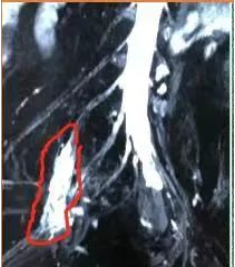

病例1:一位腓总神经损伤表现的患者,曾做过腓骨颈处腓总神经松解术,术后1年仍无恢复找我就诊。经物理查体确定病变定位在盆腔内的上骶丛神经,后经核磁检查发现上骶丛神经肿瘤(图4),综合判断为1型神经纤维瘤病,肿瘤局限在上骶丛神经。当时经后路坐骨大孔截骨手术尚不成熟,而经前路手术没有把握保证切除肿瘤后现存的下肢功能不丢失,患者决定放弃手术。3年后因肿物继续增大且出现神经压迫症状,患者曾到北京各大医院就诊,由于手术难度大,没有医生愿接手此手术,再次前来就诊,考虑到肿瘤有恶性变的潜在风险,建议手术治疗。此时我们对骶丛神经的功能解剖已融会贯通而且后侧入路手术已成熟,有信心在不影响现有下肢功能的前提下将肿瘤切除。2019年12月手术按照预先设计,经后侧坐骨大孔截骨入路显露腰骶干与S1后股上的肿瘤,将肿瘤及腰骶干后股和S1后股同时切除,而其前股成功保留,同时保留了臀上神经功能并修复了臀下神经,术后1年复查肿瘤无复发,下肢功能同手术前,充分证明我们对腰骶丛神经功能解剖的理解及手术的精准掌控已控达到了一个崭新高度(视频2)。尤其是复诊时看到患者那喜悦的心情溢于言表,我们也感到无比的欣慰和幸福。

图4 红圈内为骶丛神经肿瘤